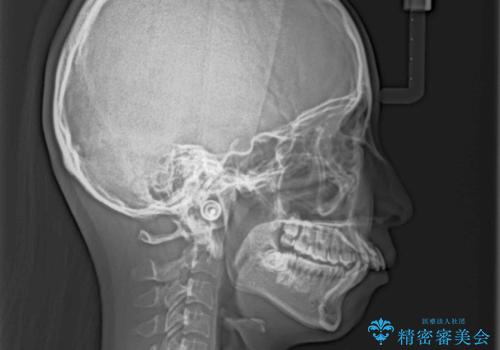

出っ歯を治したい ワイヤー装置による抜歯矯正

- 上下の出っ歯を気にして来院された患者様です。

口元を積極的に引っ込めるために、上下左右の小臼歯を4本抜歯することとしました。

右上前から2番目の歯が欠損しているため、①矯正治療により欠損部にスペースを作りインプラント補綴を行って前歯を左右対称に揃える、②左右非対称となるが、欠損補綴を行わずに排列する、のいずれかとなりますが、患者様と相談の上②にて矯正治療を行うこととしました。

変則的な歯列であったため、奥歯がしっかりと咬み合うのか、前歯はしっかりと排列できるのかと不安ではありましたが、結果としてはきれいに整った歯列にて終了することができました。